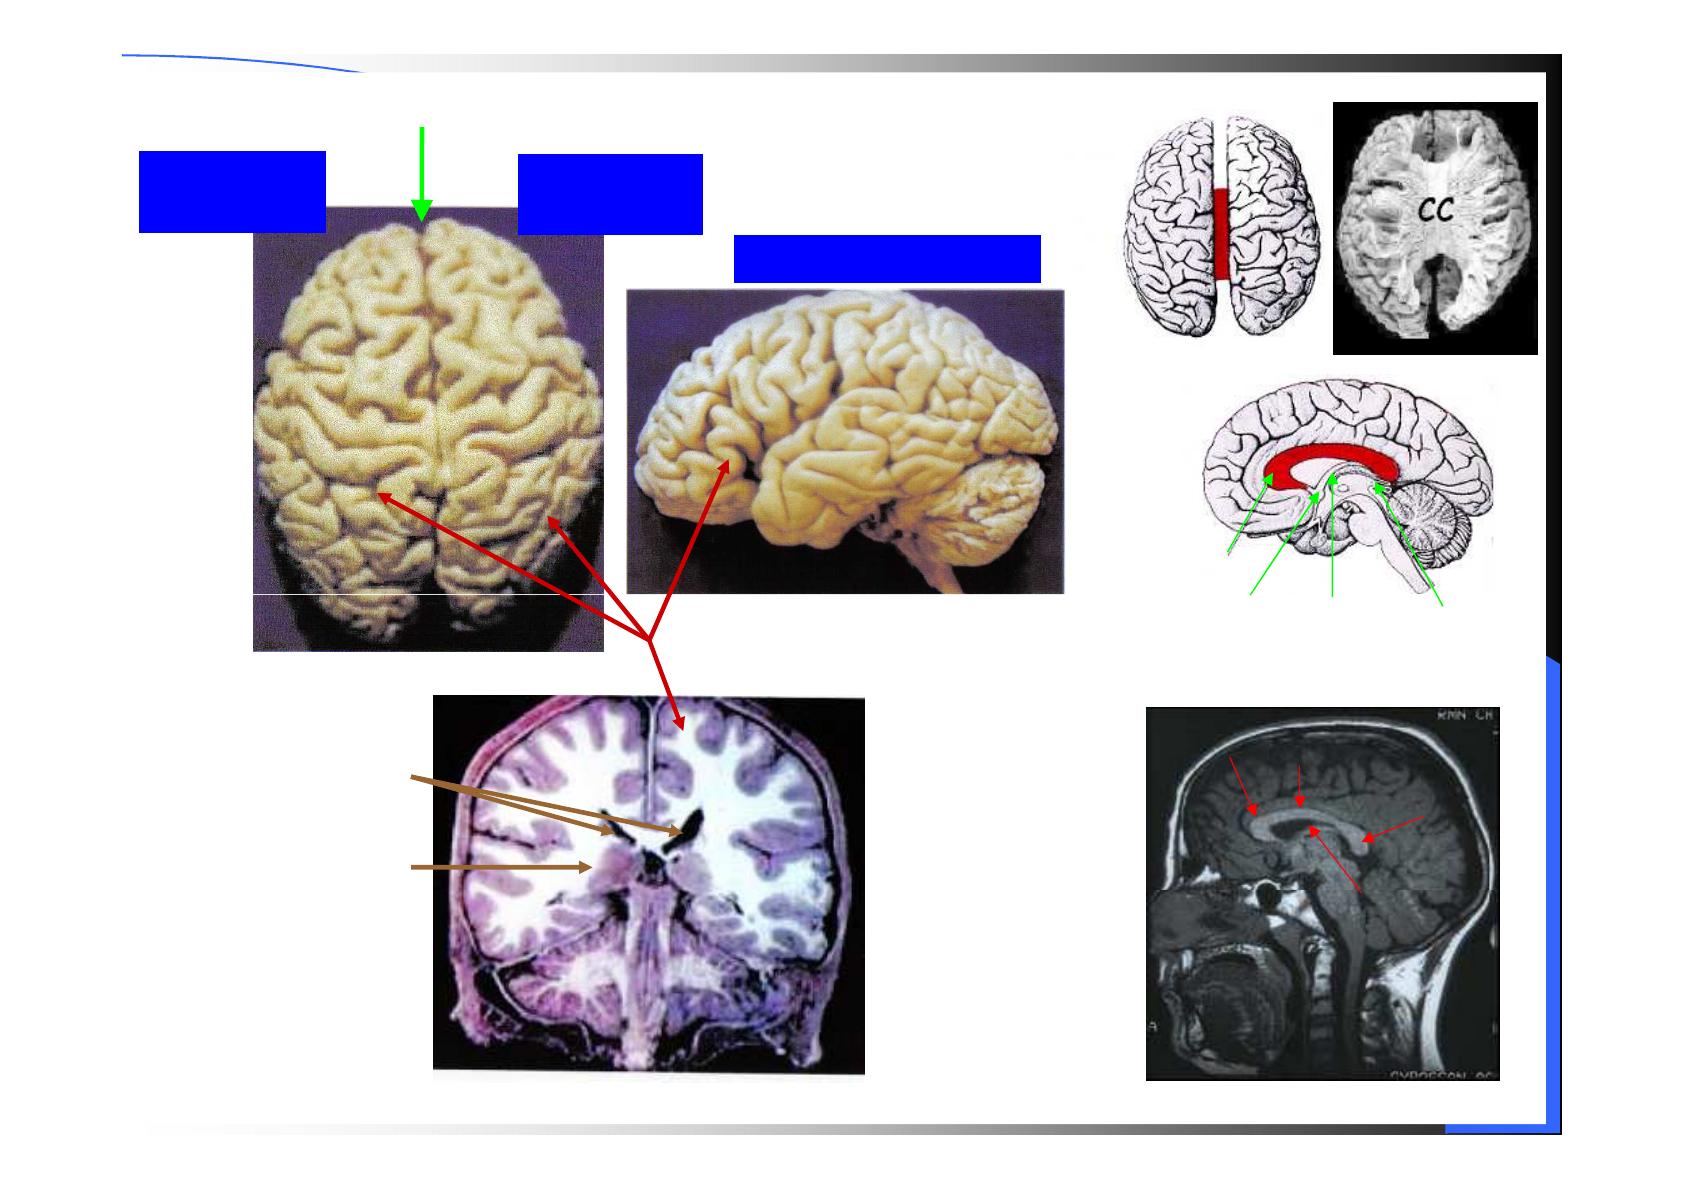

Hémisphère

gauche Hémisphère

droit

Fissure inter-hémisphérique

Hémisphère gauche

corps

calleux

Ventricules

latéraux

Structures

sous-corticales

Fornix

CA

Coupe sagittale

Genou

calleux Tronc

Splenium

Hémisphères cérébraux

Scissure centrale

Scissure

de Sylvius

pariéto-

occipitale

Lobe

temporal

frontal Lobe

pariétal

occipital

Lobe frontal

Lobe pariétal

Sillon cingulaire

calcarine

Gyrus cingulaire